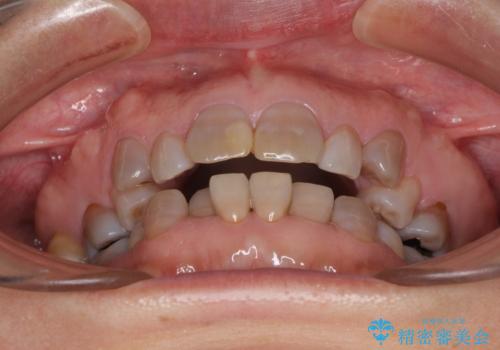

- 小さいころからの歯の変色と矯正治療の後戻りを気にして来院された患者様です。

気になる変色歯を仮歯に変え、その後歯列不正を矯正治療で改善し、最後にオールセラミッククラウンにて補綴治療することとしました。